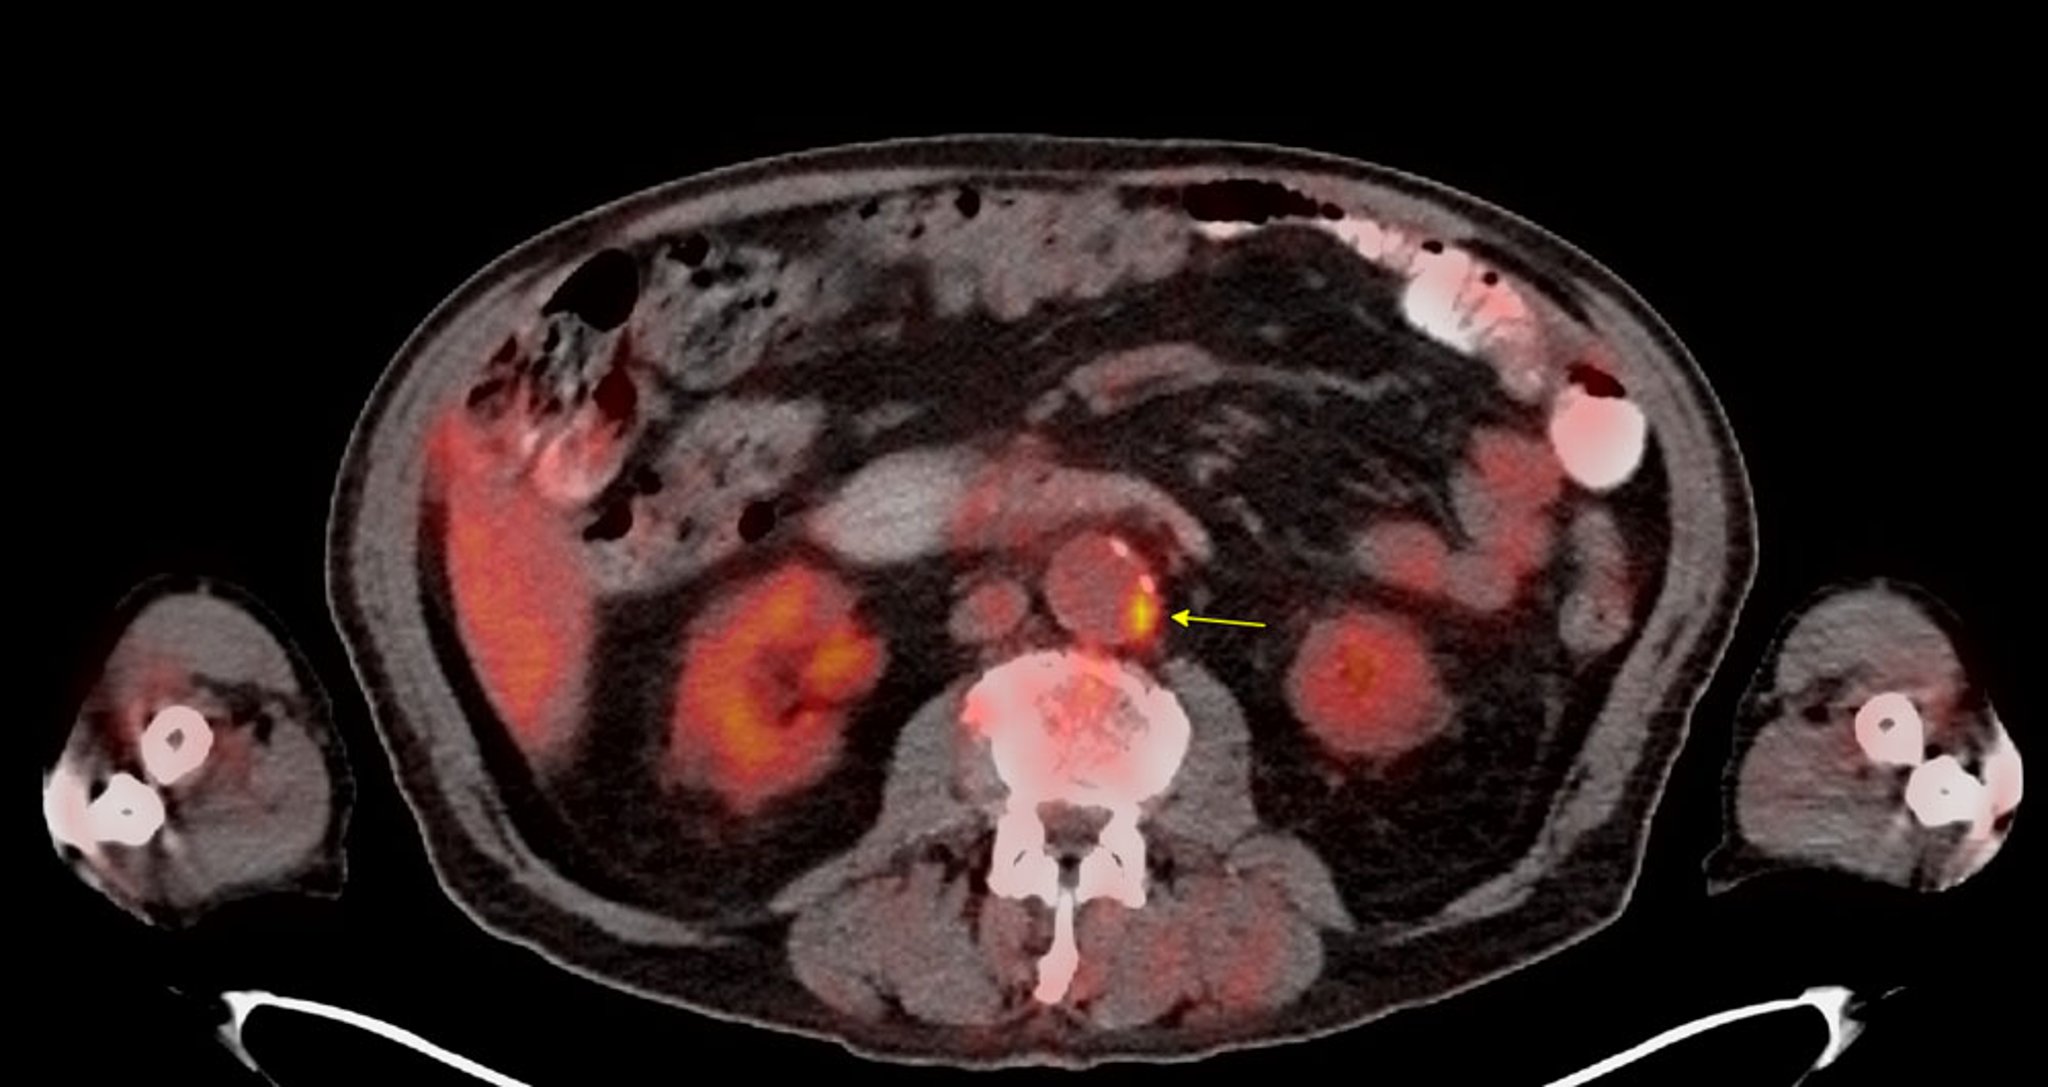

• Imageamento molecular por tomografia por emissão de pósitrons (PET): esta técnica utiliza traçadores de imageamento molecular para detectar a atividade metabólica de placas ateroscleróticas (F18-fluorodesoxiglicose [FDG]) ou microcalcificações (F18-fluoreto de sódio).